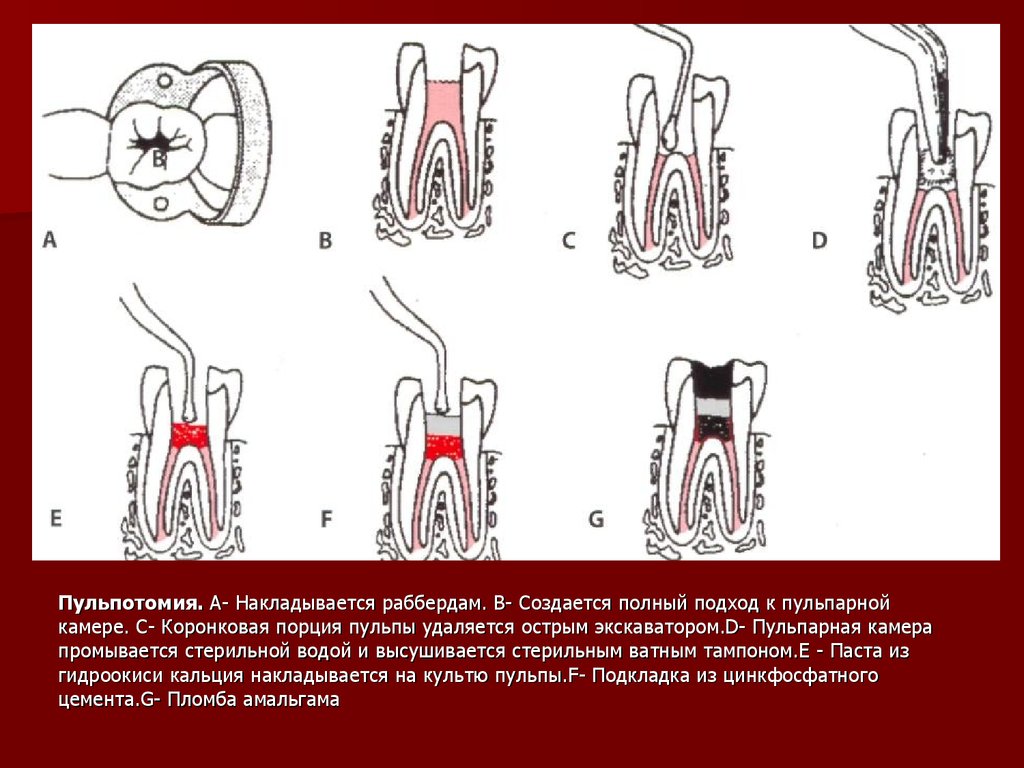

Культя зуба это

Культя зуба это 106 фото